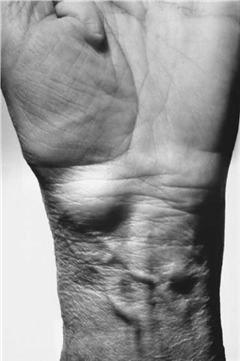

Dupuytren’s disease is a complex, benign fibroproliferative disorder of the palmar fascia that results in progressive, permanent flexion contractures of the digits. Recognized as a hallmark pathology in both adult hand surgery and as a critical differential diagnosis in pediatric hand anomalies (such as camptodactyly or infantile digital fibromatosis), mastering its diagnosis and treatment is essential for the orthopedic surgeon. The condition primarily affects the metacarpophalangeal (MCP) and proximal interphalangeal (PIP) joints, most frequently involving the ulnar digits (ring and little fingers). The clinical presentation often begins insidiously with a palpable palmar nodule, which over time coalesces into a dense, unyielding cord that physically tethers the digit into flexion, profoundly impairing hand biomechanics and patient quality of life.

The decision to intervene surgically in Dupuytren’s disease must be carefully weighed against the natural history of the condition and the functional demands of the patient. Observation is the standard of care for painless nodules or mild contractures that do not impair hand function. The classic clinical threshold for intervention is evaluated using Hueston’s tabletop test. If the patient is unable to place their palm completely flat on a hard surface, the test is positive, indicating an MCP joint contracture of at least 30 degrees, which generally warrants intervention.